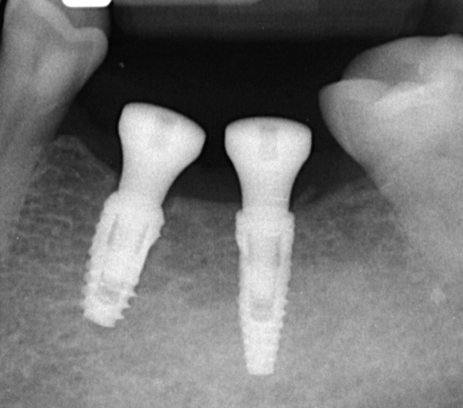

Імплантація

Імпланти — сучасний спосіб відновити зуби з максимальним комфортом та природним виглядом.